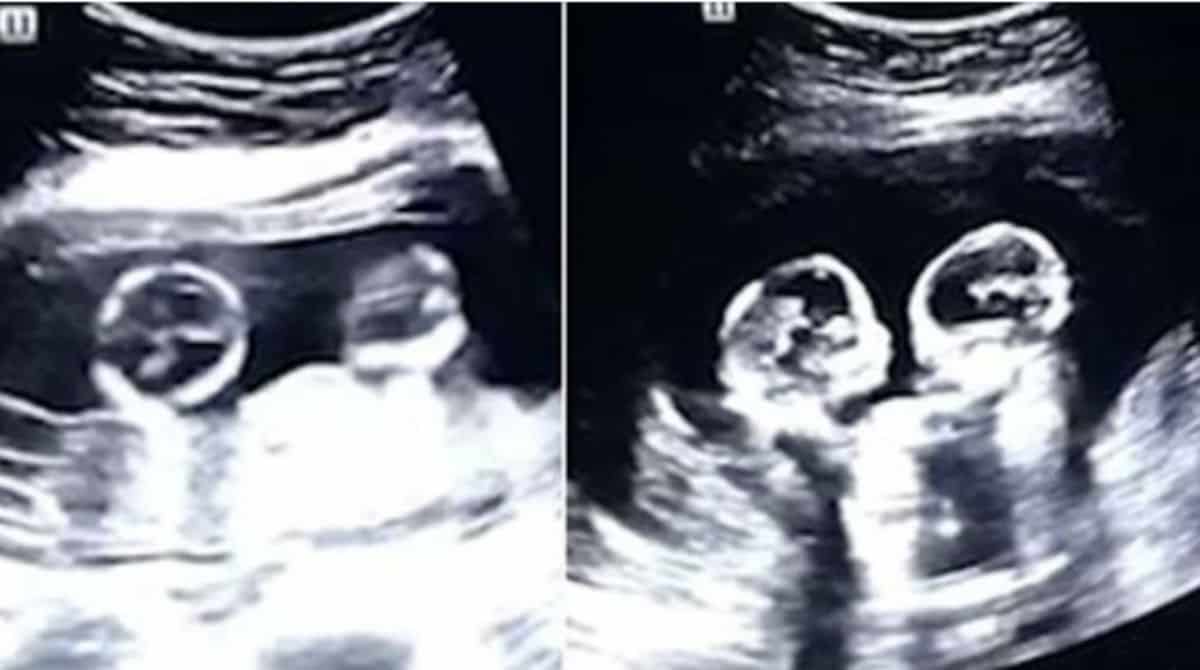

O post Ultrassom mostra irmãs gêmeas “brigando” na barriga da mãe! Veja: apareceu primeiro em Bebê Mamãe.